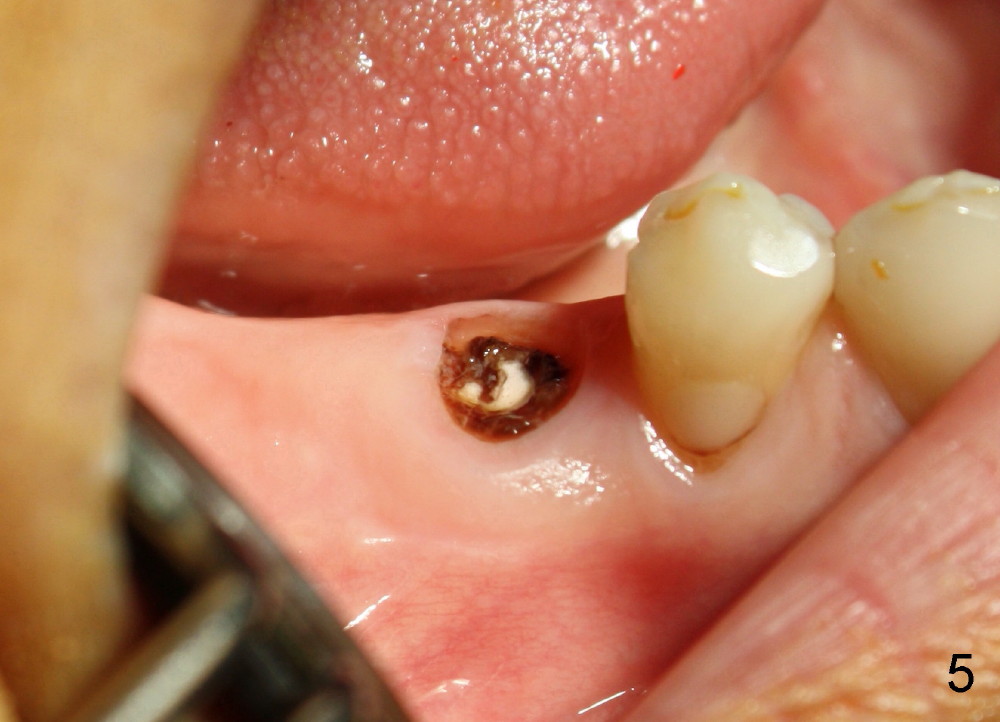

If the immediate implant (5x20 mm) is placed within the confinement of the socket, the integrity of the nerve will be not violated (Fig.4). The patient returns for the surgery 2 months after bridge removal. The root stump is cleaned so well that the buccal apical fistula disappears (Fig.5). The mesiodistal dimension of the root is 5 mm, whereas buccolingual 6.5 mm. Infiltration (not block) anesthesia is administered. The root is extracted. A 2 mm pilot drill drops by itself into the socket (Fig.6 D); the loop should overlap the apex of the socket.